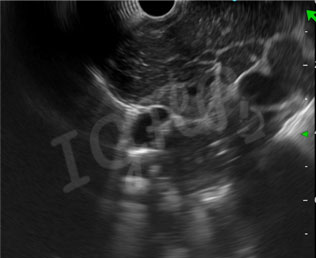

12-year-old female child with abdominal pain underwent Endoscopic Ultrasound which show presence of multiple conglomerate mediastinal lymph nodes.EUS Guided biopsy was taken from the node.

Endoscopic USG-